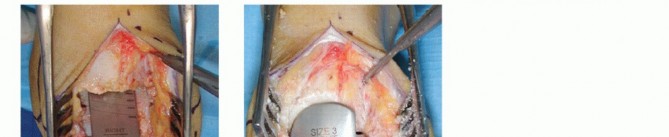

Capsulotomy and capsulectomy are done, and a self-retaining retractor is inserted to carefully keep the soft tissue mantle away (FIG 5).

FIG 5 • The ankle joint is exposed through an anterior approach.*

TECH FIG 1 • Tibial resection. Tibial resection block is adjusted taking the tibial tuberosityor the anterior spina of iliac crest as the reference in the frontal plane (A,B) and the anterior tibia in the sagittal plane (C). D. Two to 3 mm of bone is removed, as measured at the apex of the tibial plafond. E. Bone is removed and resection is finalized at the lateral side, paying attention not to damage the integrity of the fibula and at the medial side to get a sharp perpendicular cut along the medial malleolus. ## Talar Resection Positioning the Resection Block Insert the talar resection block into the tibial cutting block.